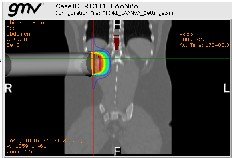

radiance, desarrollado por GMV, es el único producto en el mundo diseñado para planificar la radioterapia intraoperatoria y facilitar que el proceso sea repetible. Esta herramienta ha demostrado ser de gran importancia para los profesionales puesto que les permite realizar de una manera más fiable el procedimiento de RIO, cubriendo todas las fases de su protocolo. radiance es el perfecto instrumento de simulación y planificación para oncólogos radioterapeutas, cirujanos, físicos así como otros profesionales de la RIO.

radiance, permite planificar la distribución y la dosis de radiación, entre otros parámetros críticos para el tratamiento de cada paciente específico . radiance, desarrollado por GMV, líder en el desarrollo y la aplicación de innovación y tecnologías avanzadas, en colaboración con el grupo de investigación del Hospital General Universitario Gregorio Marañón, junto con un conjunto de prestigiosos hospitales y universidades españolas, facilitará al especialista el análisis completo del paciente y la toma de decisiones previa a la intervención quirúrgica, dando lugar a la identificación del tratamiento óptimo para cada paciente.